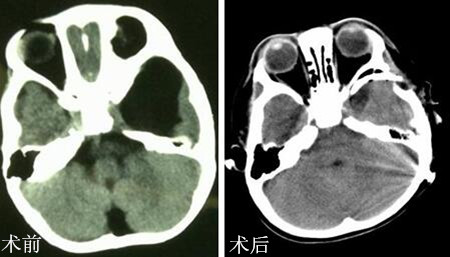

颅脑MRI检查提示:1.左侧颞极至外侧裂区蛛网膜囊肿;2.左侧后组筛窦及蝶窦少许炎症。脑脊液流速测定:部位为左侧颞极-外侧裂区病灶未见明显正弦波,与三脑室不同步。诊断:左侧颞极蛛网膜囊肿。

完善相关检查,排除手术禁忌症,小儿神经外科成功为患儿实施“左侧颞极蛛网膜囊肿切除术”。术后患儿恢复良好,术后15天顺利出院。手术后5月复查CT显示囊肿基本消失。